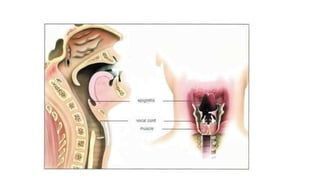

Abnormal changes in the voice are called hoarseness.

When hoarse, the voice may sound breathy, raspy,

strained, or show changes in volume or pitch (depending

on how high or low the voice is). Voice changes are

related to disorders in the sound-producing parts (vocal

folds) of the voice box (larynx). While breathing, the vocal

folds remain apart. When speaking or singing, they come

together and, as air leaves the lungs, they vibrate,

producing sound. Swelling or lumps on the vocal folds

hinder vibration, altering voice quality, volume, and pitch.

Hoarseness Abnormal changes inthe voice are called hoarseness. When hoarse, the voice may sound breathy, raspy, strained, or show changes in volume or pitch (depending on how high or low the voice is). Voice changes are related to disorders in the sound-producing parts (vocal folds) of the voice box (larynx). While breathing, the vocal folds remain apart. When speaking or singing, they come together and, as air leaves the lungs, they vibrate, producing sound. Swelling or lumps on the vocal folds hinder vibration, altering voice quality, volume, and pitch.